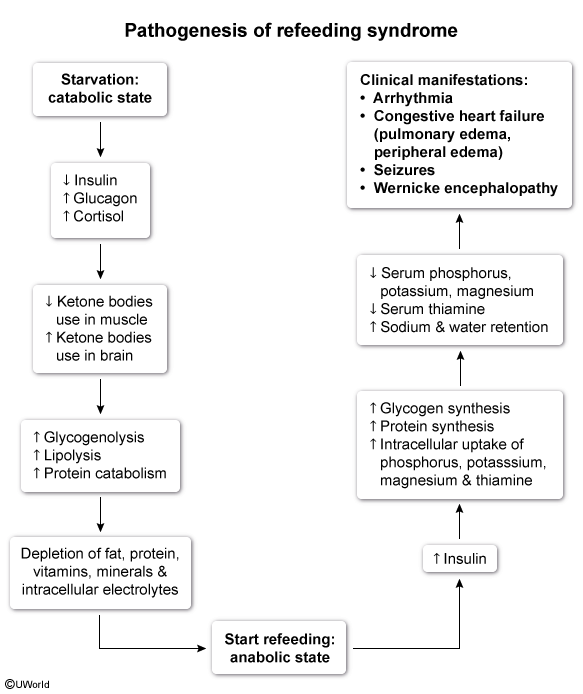

what is the causative agent of refeeding syndrome?